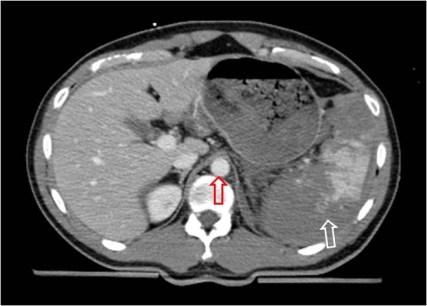

SIGNO DE LA VENA CAVA INFERIOR PLANA

Signo de hipovolemia en la TC abdominal. El colapso de la vena cava inferior (flecha roja) indica disminución del retorno venoso que puede requerir administración urgente de líquidos y monitorización de la presión venosa central. Se define por un diámetro anteroposterior menor de 9 mm en al menos tres cortes consecutivos. El caso es el mismo del primer ejemplo del signo anterior, en un corte más caudal.Podemos ver el bazo roto (flecha blanca) y líquido libre en el espacio hepatorrenal o de Morison (flecha negra).

Podemos ver otro ejemplo en la segunda imagen del Signo de la aorta pequeña.